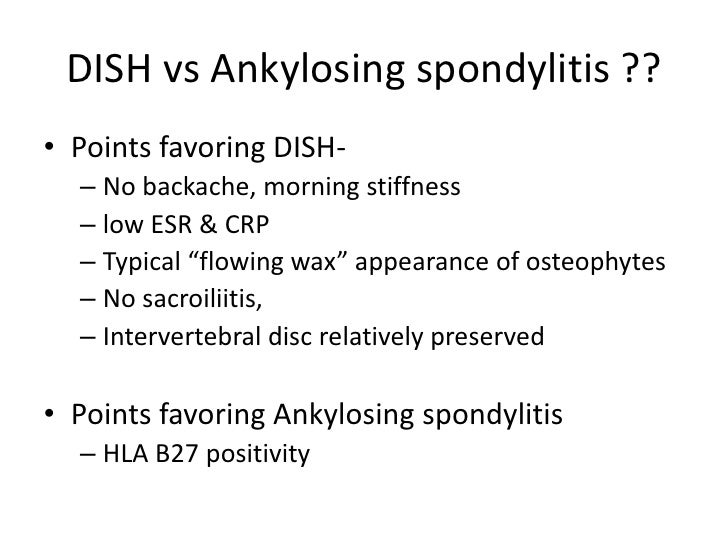

Even low energy trauma could lead to a serious fracture. So someone with the condition suffers a fall and lands on their back has an increased risk of a fracture. A healthy spine is flexible enough to distribute the force from a fall or hit and prevent injury. It is usually asymptomatic/without symptoms or mildly symptomatic. Diffuse Idiopathic Skeletal Hyperostosis Symptomsĭiffuse Idiopathic Skeletal Hyperostosis SymptomsĪn important reason that diffuse idiopathic skeletal hyperostosis is not recognized and underdiagnosed is that many individuals do not experience symptoms.